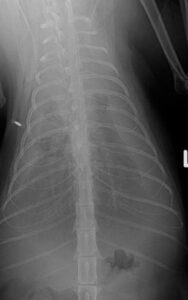

↑ 上の絵は、ワンちゃんの背骨にレーザー治療を行っているイメージ図です。 犬 トイプードル 13歳 オス(去勢手術済み)  【 抱っこすると痛がる、震えているという症状 】で来院されました。 …